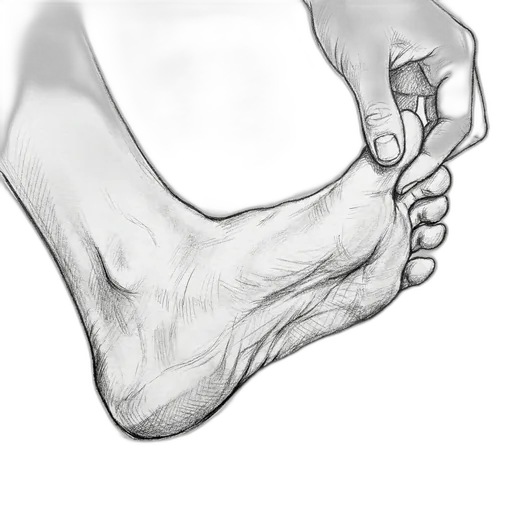

Windlass Stretch

This stretch works the plantar fascia — the thick band of tissue that runs along the bottom of your foot from your heel to your toes. Think of it like a bowstring that supports your arch. When you pull your big toe back, you're gently tightening and lengthening that band, which helps it heal, stay flexible, and reduces that sharp "first step" pain many people feel in the morning.

What to expect: Within 2–3 weeks of daily stretching, most people notice that morning heel pain starts to ease. By 6–8 weeks, the "first step" pain is often significantly reduced or gone. You should be able to stand up after sitting without dreading that first step.

How to do it: Sit down and cross the affected foot over your opposite knee. Grab your big toe and gently pull it back toward your shin — you'll feel a stretch along the bottom of your foot. You can use your other hand to feel the fascia tighten like a guitar string along your arch.